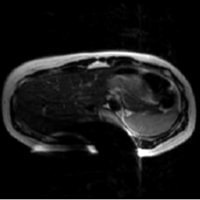

患者様を案内又は搬送する際は、患者様の金属の有無について十分注意をお願いします。金属が体内に入っている方や、 身につけている方は写真上に影響が出ると同時に体内金属が動いたり、発熱したりする場合があり危険な場合があります。 金属があった場合の症例を提示します。

下着の金具による影響